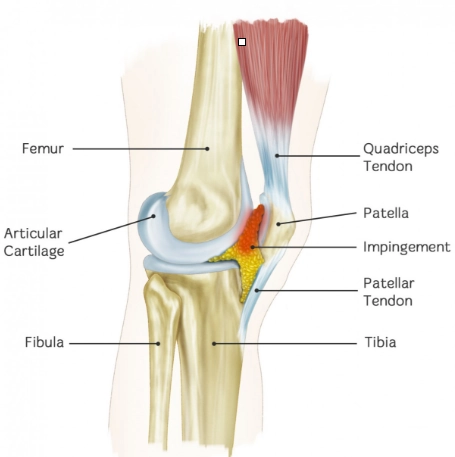

Hội chứng chèn ép túi mỡ Hoffa (Hoffa fat pad impingement syndrome)

Hội chứng chèn ép túi mỡ trên bánh chè (Anterior suprapatellar fat pad impingement syndrome)

Hội chứng chèn ép túi mỡ trước đùi (Prefemoral fat pad impingement syndrome)

Thoát vị túi mỡ Hoffa (Hoffa fat pad herniation)